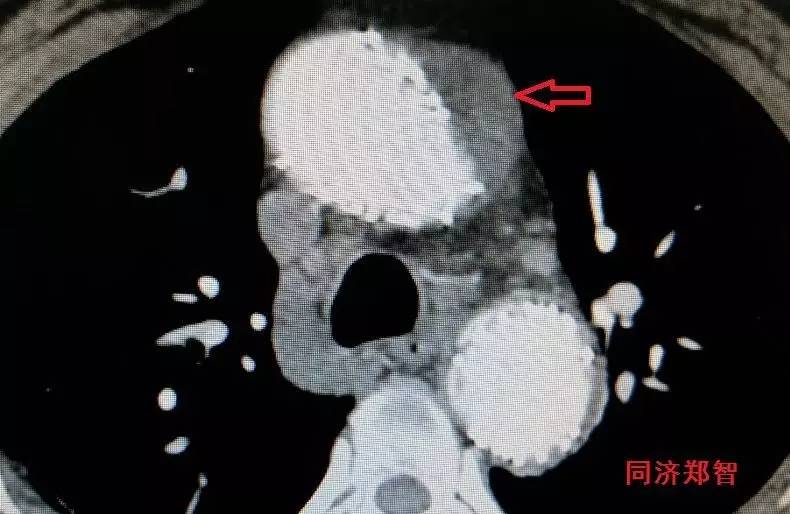

胸降主动脉穿透性溃疡合并壁间血肿(图6),心底层面红箭头所示。

图6